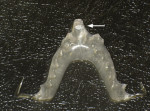

Biomechanical: Significant tooth structure loss had occurred between 2009 and 2017 (Figure 1 through Figure 3). Severe attrition had occurred on the anterior teeth, especially tooth No. 11. Severe erosion and abrasion were present on teeth Nos. 11, 18, 20, 21, 28, 29, 31, and 32 (Figure 4). The patient had generalized sensitivity, and tooth No. 18 was painful due to deep erosion, which approached the pulp chamber. Teeth Nos. 7 and 10 had moved out of position and rotated (Figure 5). The progression of erosion over the 8-year period could also be seen radiographically and was especially noticeable on tooth No. 18 (Figure 6 and Figure 7). The occlusal resins were lost on the mandibular molars, and the erosion and abrasion from the opposing crowns continued to erode the tooth structure.

Functional: Attrition was noted on the teeth that were not protected with full-coverage crowns (Figure 8 and Figure 9). While wearing a Kois deprogrammer for about 1 month prior to restorative treatment, the mandibular teeth wore a notch in the deprogrammer platform, confirming clenching and the possibility of an impaired cortical control of the central pattern generator (Figure 10).1 All platform variables were verified and proper design of the Kois deprogrammer was followed. (The notch in the deprogrammer was repaired, leaving a smooth, flat surface to allow the proper position of the mandible to be determined.) The temporomandibular joint examination revealed normal opening with no joint sounds. The load and immobilization tests were normal. All the muscles, except the masseter, had no tenderness to palpation. Trigger points were palpable within the masseter muscles, which were hypertrophied. The diagnosis was determined to be occlusal dysfunction with the addition of awake bruxism and clenching. Upon questioning, the patient shared that he clenched while playing tennis daily, which he was very passionate about. The evidence that he was not grinding at night was the fact that tooth No. 11 was extremely cupped and not flattened. This ruled out a diagnosis of sleep bruxism, as the incisal edge would have become flat due to lateral movements of the mandible.